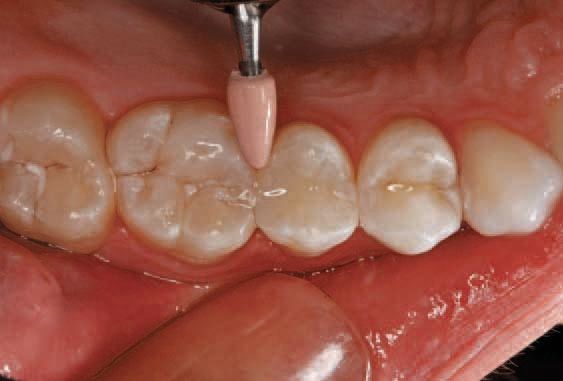

Green polishing points were used to polish the surface (Fig. 12). Pink polishing points were used to achieve a high gloss (Fig. 13). Because the optical properties of this material are designed specifically to match the refractive index of the fillers and polymer matrix, the restoration appeared imperceptible from the surrounding tooth structure because of the enamel-like translucency of 15%.